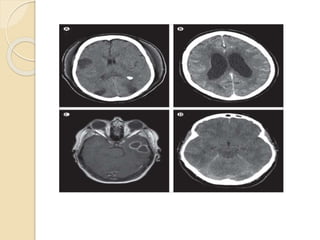

3. CT Scan

Cranial computed tomography (CT) is of

limited use in acute bacterial meningitis

. CT in cerebral oedema may show slit-

like lateral ventricle and areas of low

attenuation.